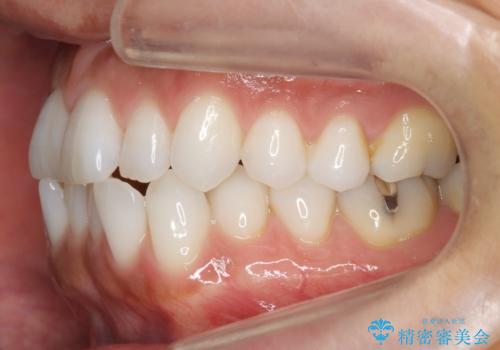

30代女性 前歯のがたつき

- 30代女性

- 前歯のがたつきを主訴に来院。

右下の奥の銀歯も治療しています。

- 115.5万円 矯正治療 85万円、奥歯ジルコニアクラウン11万円(ZrCr 10万円、仮歯1万円、矯正用仮歯2万円)セラミックインレー7万円費用は治療当時の料金となります

下の前歯を下げるため、IPR(歯をわずかに削る処置)を行っています。